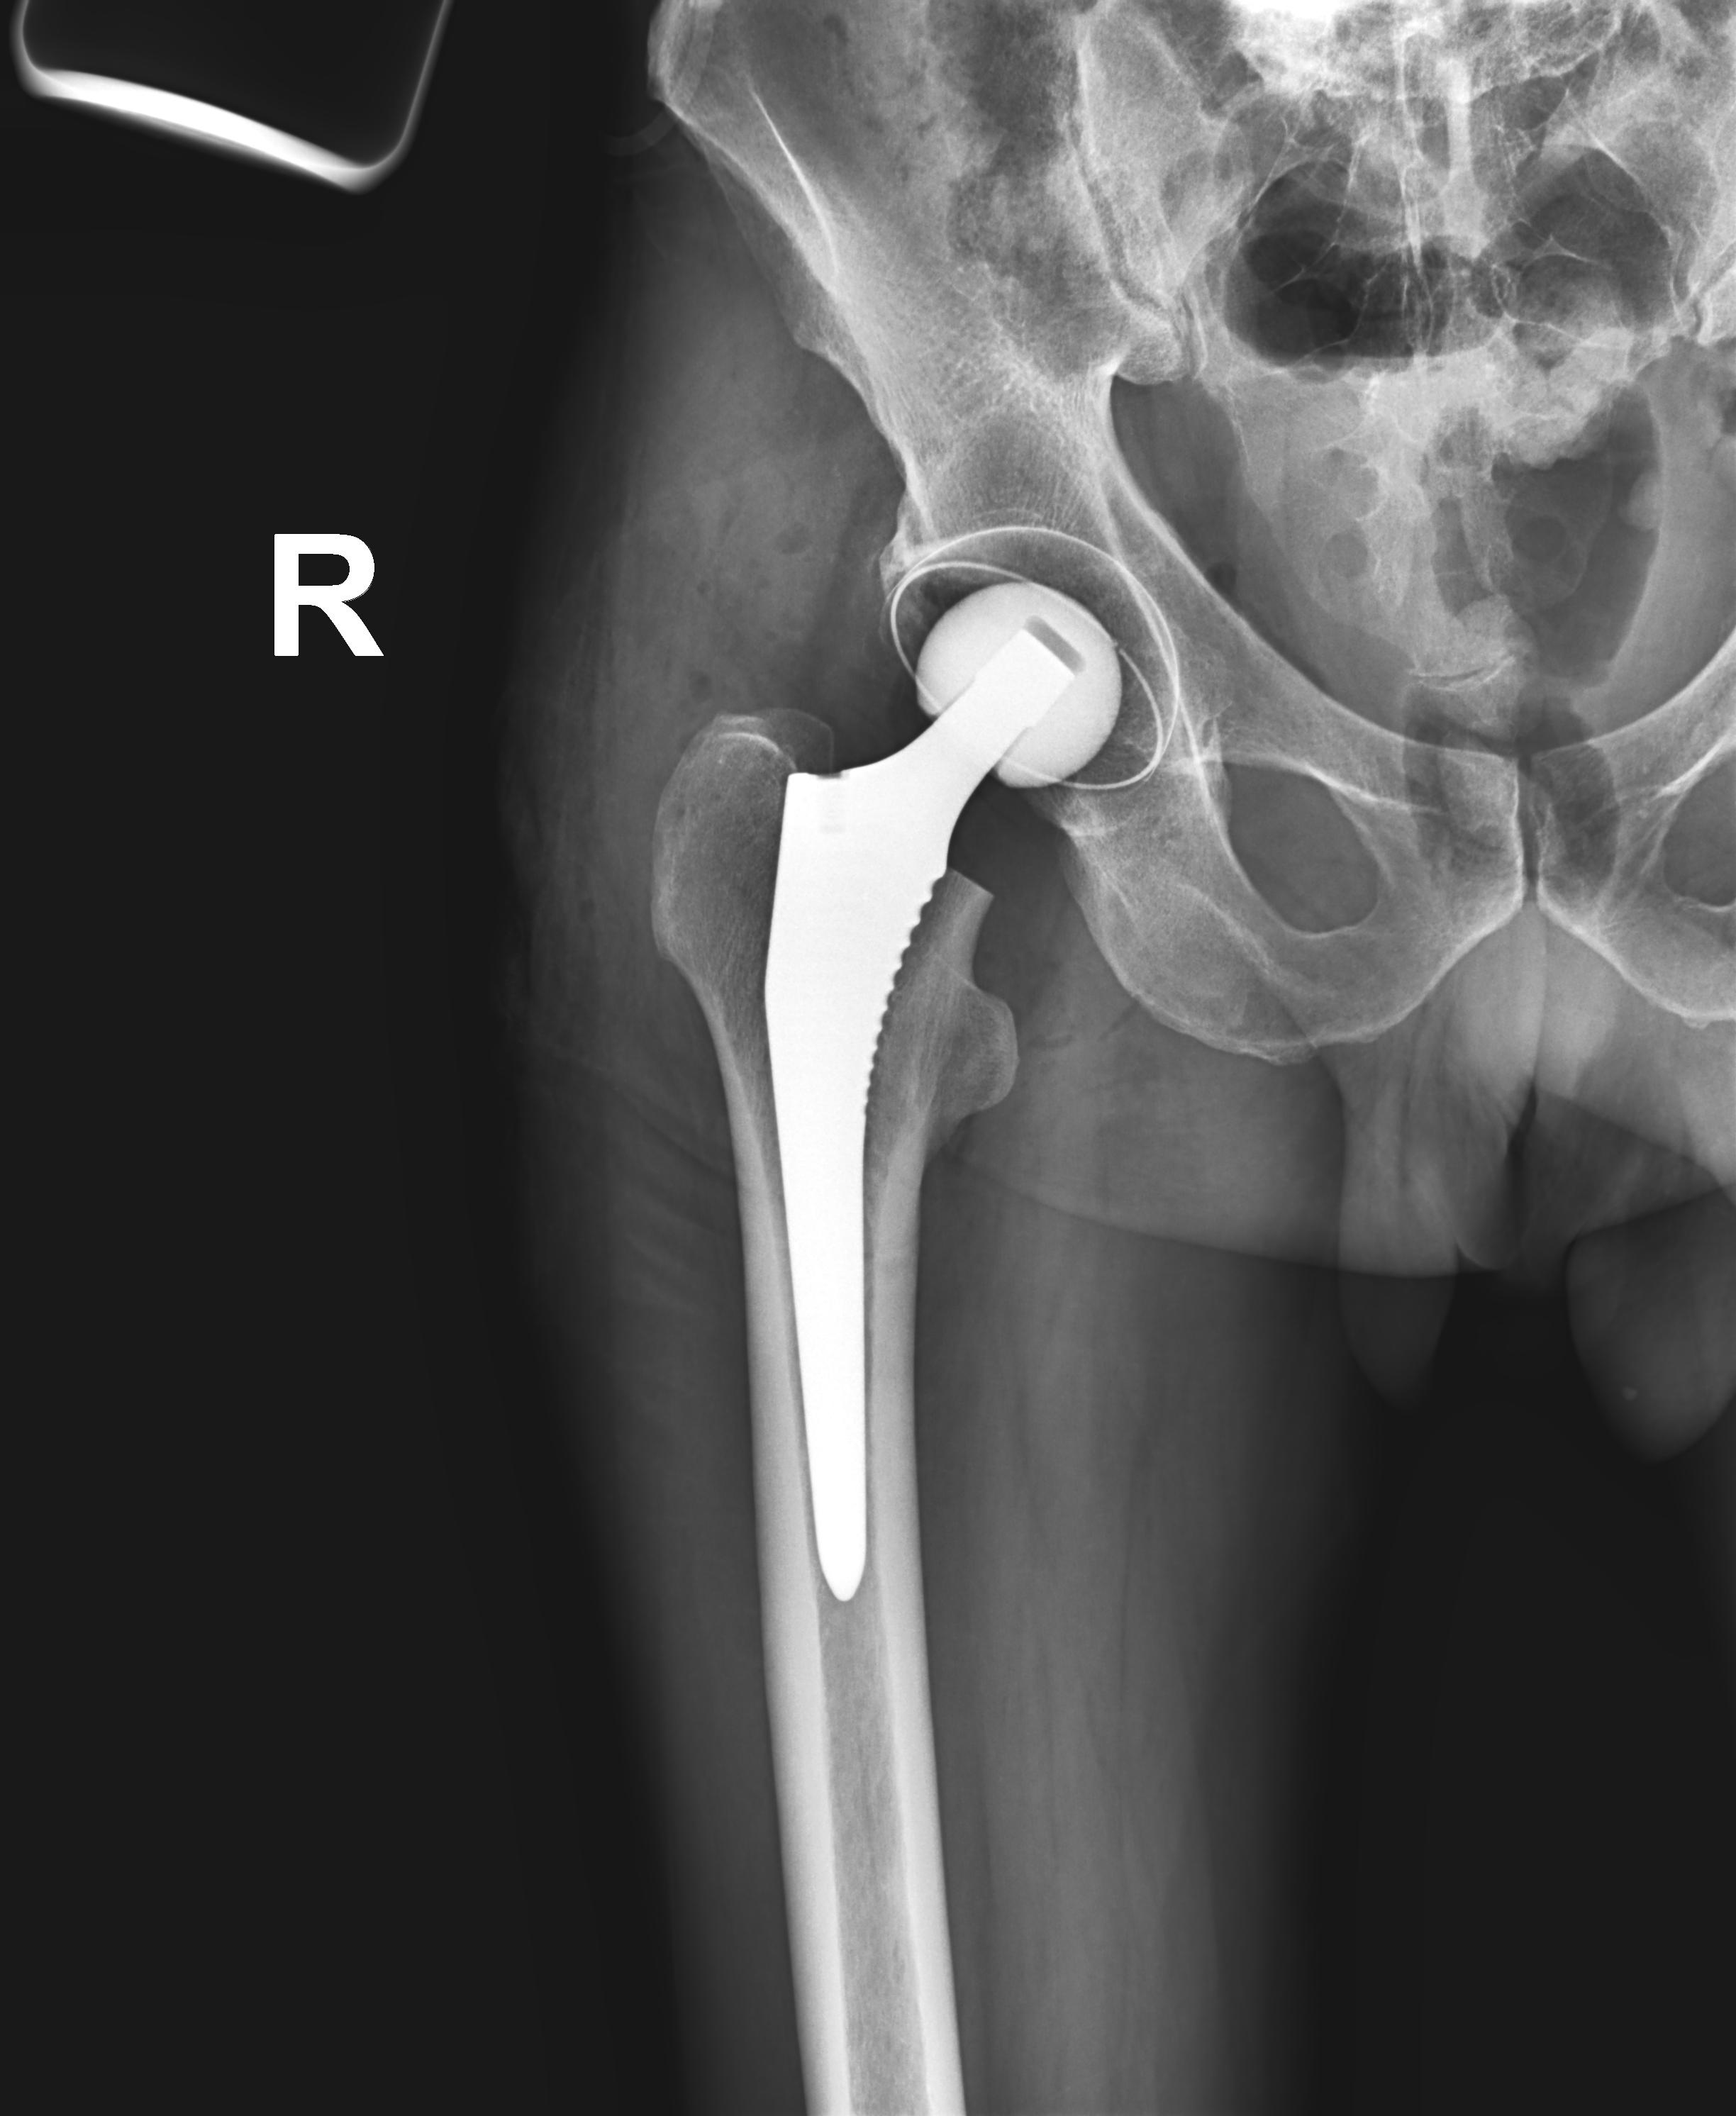

Эндопротезирование тазобедренного сустава